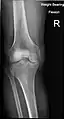

Fractures

Radiography to examine possible fractures after a knee injury

Knee fractures are rare but do occur, especially as a result of a road accident. Knee fractures include a patella fracture, and a type of avulsion fracture called a Segond fracture. There is usually immediate pain and swelling, and a difficulty or inability to stand on the leg. The muscles go into spasm and even the slightest movements are painful. X-rays can easily confirm the injury and surgery will depend on the degree of displacement and type of fracture.

X-ray